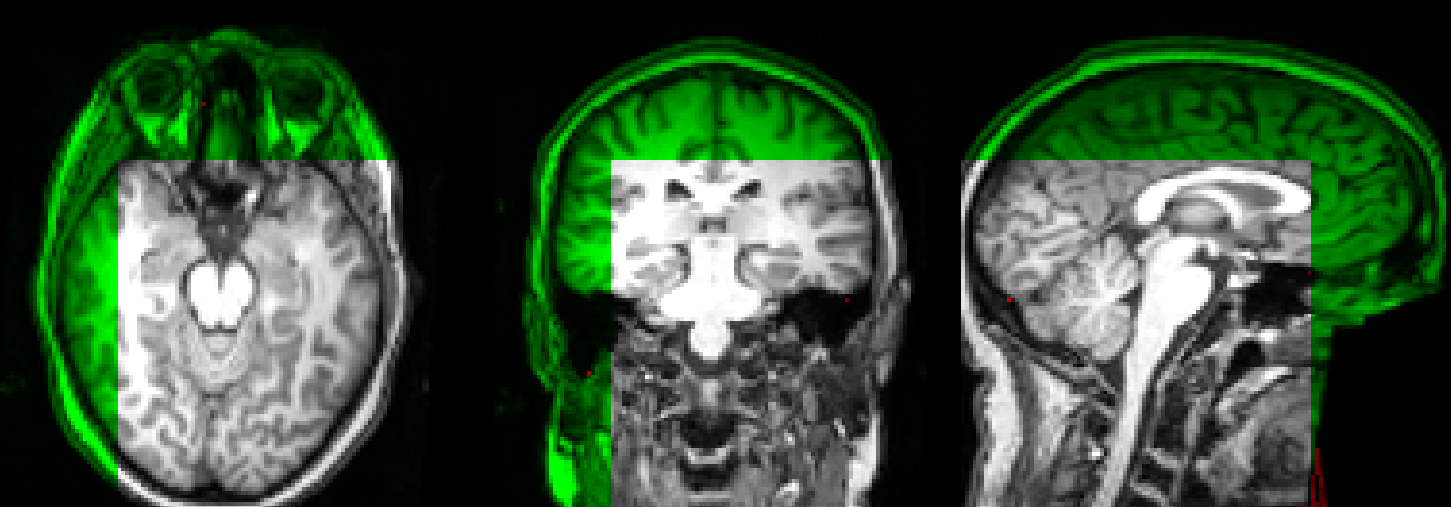

Nice! I tested it with the samples above and looks good to me. Thanks for pushing out these improvements! I can also confirm that differently sized image do not work. I padded the reference image with an adjusted affine: The green image is the ITK output (where the registration also failed - not really sure why, this should have been easy), the gray image is the output when applying the returned affine. So for the meantime I added a check: if reference_image and np.any(self.image_size != reference_image.image_size):